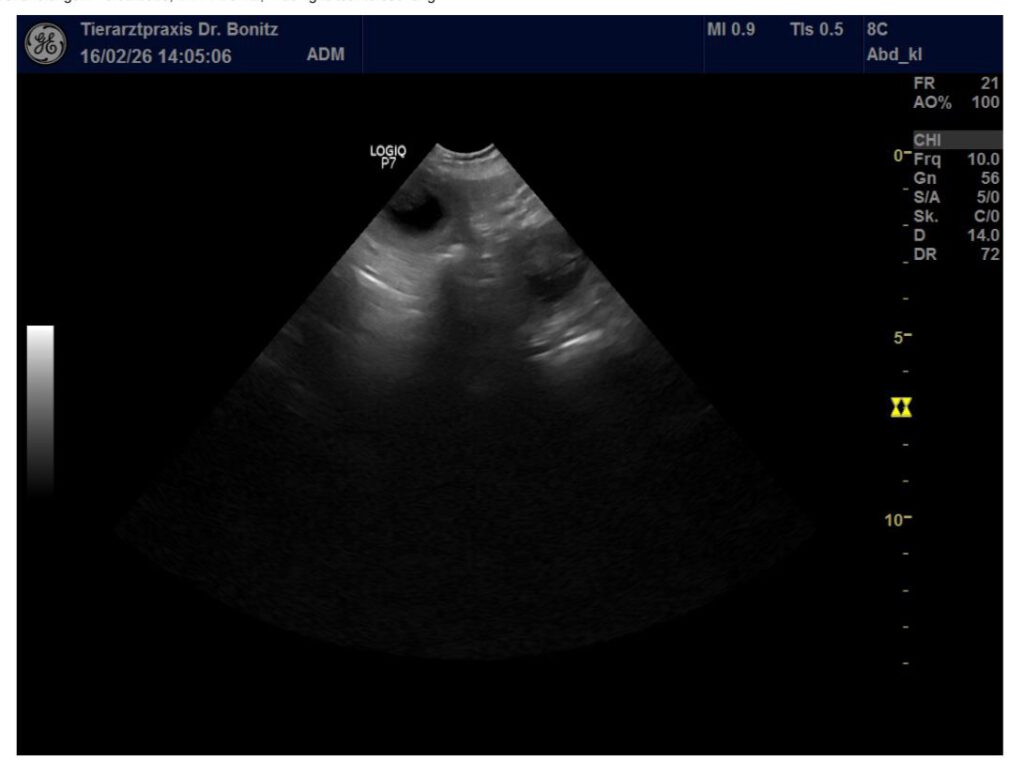

Wir waren am 17.02.2026 beim Trächtigkeitsultraschall und es konnten mindestens 4-5 Welpen gezählt werden. Die Entwicklung ist dem Trächtigkeitszeitpunkt entsprechend. Sheena lässt sich bisher noch immer nichts anmerken, was aber auch hier normal ist.